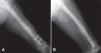

Todos los pacientes fueron llevados a cirugía bajo anestesia general o conductiva, colocando al paciente en posición de decúbito lateral. El procedimiento se inició retirando los tornillos de bloqueo distal o proximal para permitir compresión en el foco de no unión. En cuanto al foco de fractura, por la cara lateral del muslo, se realizó una incisión de 12 cm; al llegar al foco de fractura, se retiró todo el tejido fibroso y los fragmentos avasculares, y se comprobó la inestabilidad rotacional con un movimiento de rotación lateral y medial de la cadera. La fractura no consolidada fue fijada en una posición que permitiera las rotaciones normales comparadas con el lado contralateral sano. Se colocó la placa en la cara lateral del fémur, anterior o posterior según el espacio disponible para colocar tornillos de acuerdo con la radiografía lateral preoperatoria. Se escogió una placa de 8 a 10 agujeros de compresión dinámica estrecha para tornillos de cortical de 4,5mm; en algunos casos de osteoporosis marcada, se utilizó una placa bloqueada o una de 3,5mm, de acuerdo con la edad del paciente y el diámetro del hueso. Los 2 primeros tornillos, uno en cada fragmento óseo, se colocaron excéntricos y tomaron las 2 corticales (medial y lateral) para garantizar un efecto de compresión dinámica. Se utilizaron al menos 3 tornillos en cada fragmento, y se agregaron los injertos óseos alrededor del foco de fractura (figs. 1–4).

La cirugía de colocación de la placa antirrotatoria se realizó en promedio 14,5 meses después de la fractura (DS = 14,4), con una mediana de 10 meses y un rango entre 9 y 28 meses. Se usaron placas DCP de 4,5mm (94%) y de 3,5mm (6%). La fijación se hizo en promedio con 7 tornillos, 13 corticales, además de usar injertos óseos en el 92% de los casos. La única complicación que hubo después de esta cirugía fue la infección del sitio operatorio en un paciente (2%). A los seis meses del tratamiento de la pseudoartrosis con la cirugía de aumentación con placa antirrotatoria e injertos óseos autólogos, la consolidación fue completa en 44 fracturas (92%).